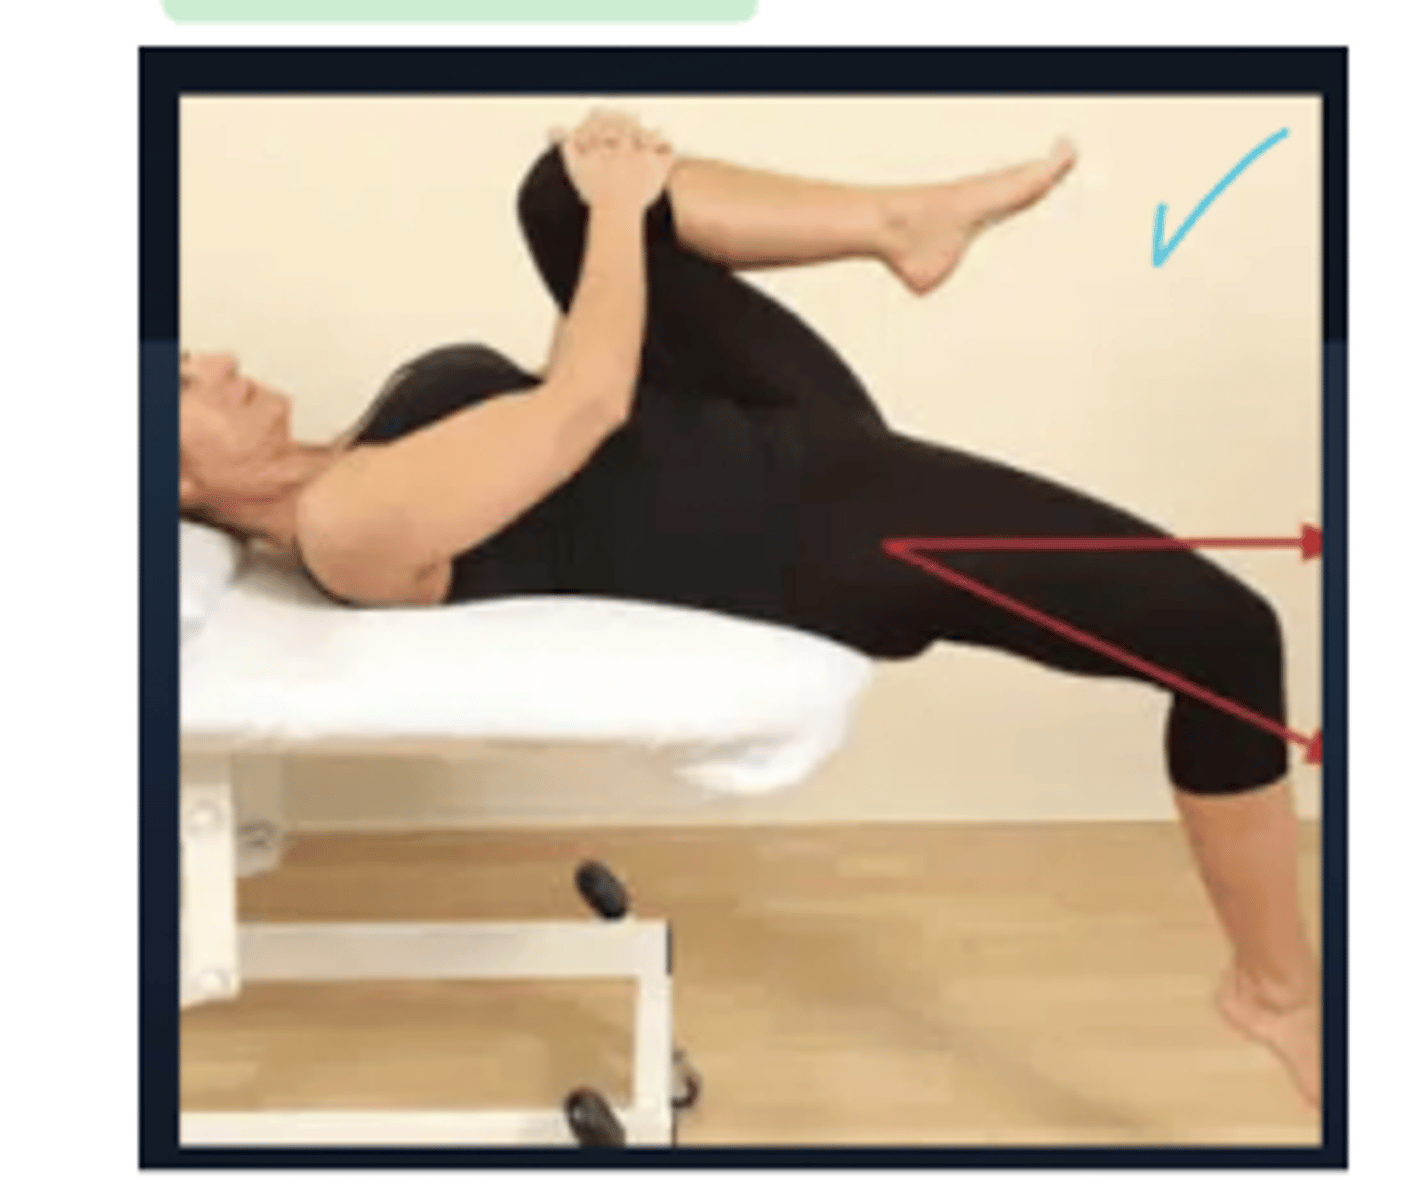

Modified Thomas Test

Iliopsoas - 1 joint muscle → if high is parallel or below the table this is good

Rectus femoris - 2 joint muscle → amount of knee flexion, if its a large angle its probably tight

TFL → IR means tightness

Sartorius → ER means tightness